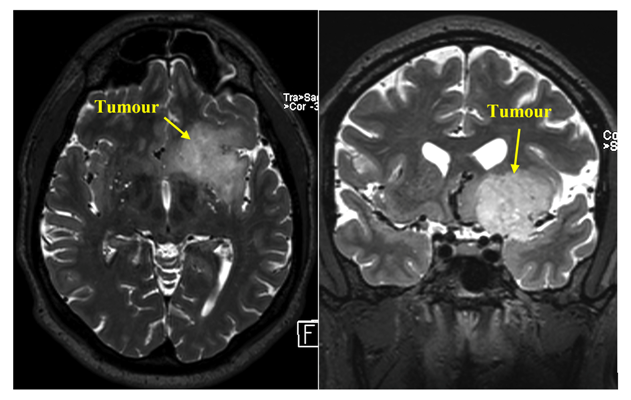

În decembrie 2014, pacientul S., 43 ani, a fost diagnosticat cu Tumoare intracerebrală. Localizarea tumorii s-a dovedit a fi una foarte dificilă, motiv din care a fost refuzat pentru tratament în alte instituții medicale. Pacientul însă a insistat asupra unei opinii secundare, ajungând în final la consultație în secția Neurochirurgie SCR. După un șir de investigații suplimentare și examinări preliminare, pacientului i s-a propus cea mai rațională variantă de rezolvare a problemei. Procesul de tratament a fost divizat în 2 etape. În cadrul primei etape, era necesar de a preleva câteva fragmente de țesut cerebral patologic (tumoare), după care medicii, de comun acord cu rudele pacientului, urmau să se pronunțe asupra posibilității de tratament radical al procesului.

„Localizarea tumorii este extrem de dificilă. Patologia implică regiunea insulară a creierului din partea stângă, arterele mari ale fisurii silviene, fibrele motorii ale tractului cortico-spinal și câteva alte structuri importante ale creierului. Localizarea din partea stângă complică și mai mult situația, deoarece mâna dreaptă a pacientului e cea dominantă, iar o intervenție chirurgicală nereușită ar putea duce la un deficit neurologic devastator pentru pacient. În pofida celor enumerate, și pentru astfel de pacienți există o șansă. Prima etapă constă în determinarea gradului de malignitate a procesului, iar în funcție de rezultatul obținut, vom planifica următorii pași”, ne-a relatat profesorul Aurel Bodiu, șeful secției de neurochirurgie a Spitalului Clinic Republican.